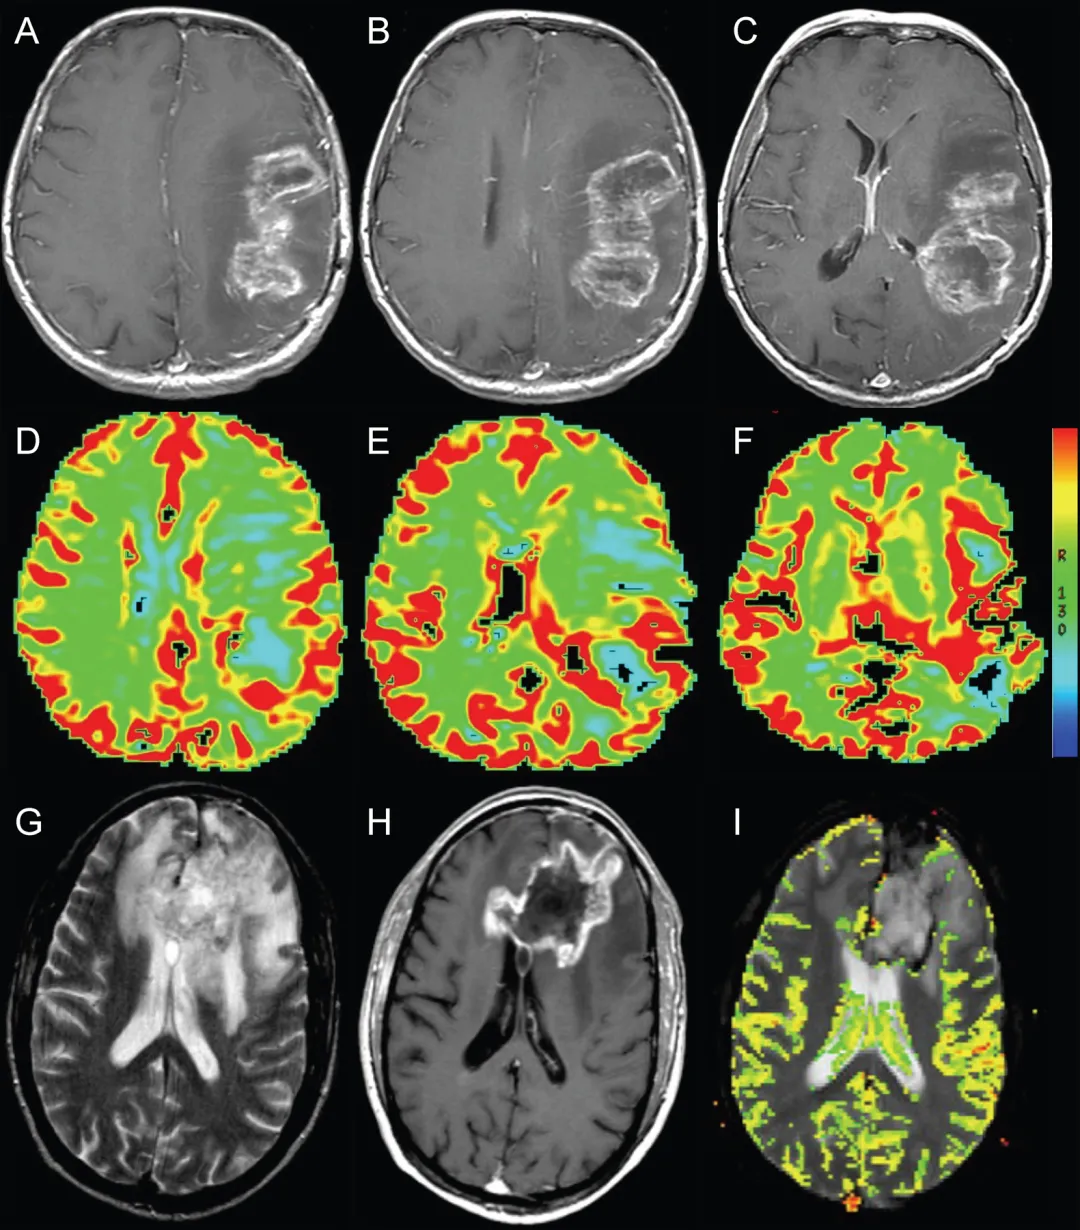

图1. 假性进展典型病例

左侧额顶叶GBM轴位T1加权增强MRI图像:

A. 活检后、放疗前图像显示左侧额叶后部脑室旁GBM

B. 外照射放疗结束后1周图像显示占位效应显著加重,邻近脑室受压

C. 放疗结束后3个月图像显示占位范围及占位效应显著消退

图2. 动态磁敏感对比灌注成像辅助鉴别假性进展

A-C:左侧额顶叶胶质母细胞瘤放疗后即刻轴位T1加权增强MRI,显示环形强化坏死性占位伴周围水肿及占位效应(与图1为同一患者)

D-F:轴位动态磁敏感对比灌注图像显示强化病灶后缘血容量轻度增加(箭头所示)

G:轴位T2加权MRI显示放疗后左侧额叶环形强化坏死性占位周围显著水肿,疑似肿瘤复发

H:轴位T1加权增强MRI显示结节状环形强化占位伴坏死

I:轴位动态磁敏感对比灌注图像未见血容量升高,符合假性进展病理诊断